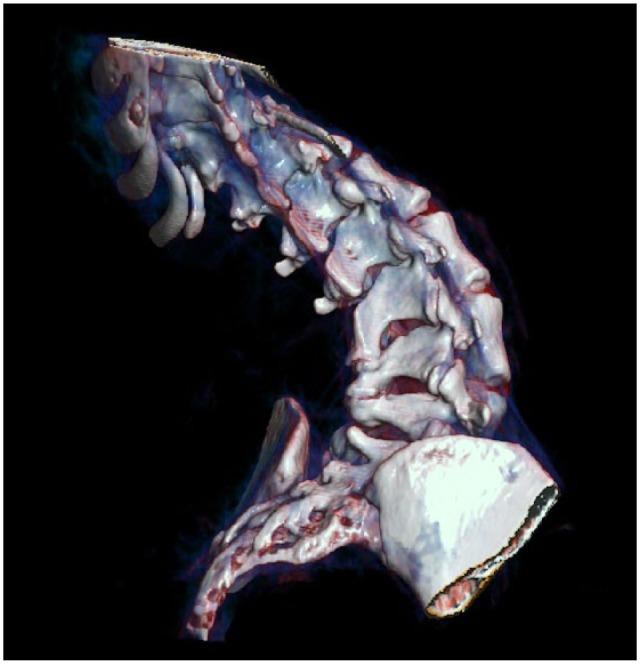

Cervical puncture to deliver nusinersen in patients with spinal muscular atrophy.

Neurology. 2018 Aug 14;91(7):e620-e624. doi: 10.1212/WNL.0000000000006006. Epub 2018 Jul 13.

Orthopedic Management of Scoliosis by Garches Brace and Spinal Fusion in SMA Type 2 Children.

J Neuromuscul Dis. 2015 Nov 21;2(4):453-462. doi: 10.3233/JND-150084.